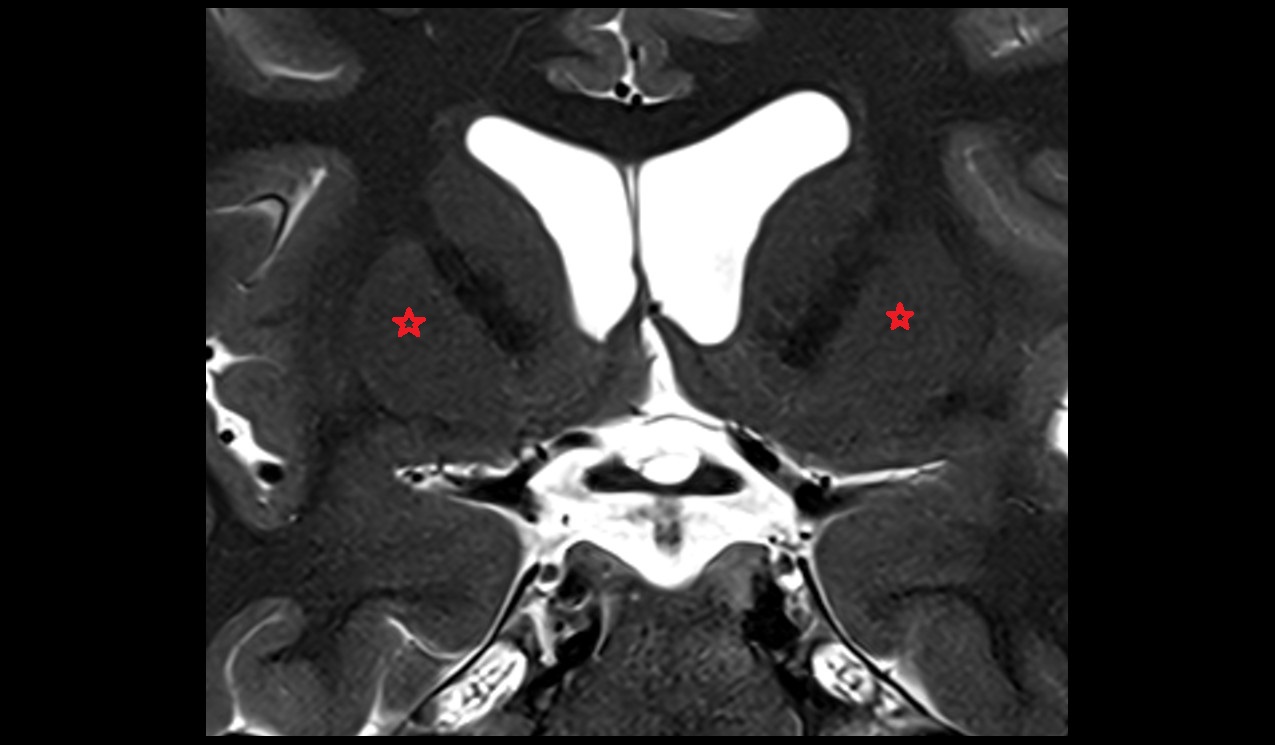

- Temporal horn of lateral ventricle